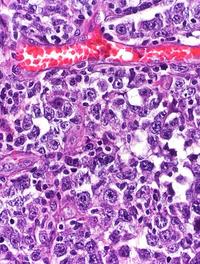

Le cancer appendiculaire à cellules caliciformes (KCC) est une entité rare de tumeur endocrine composée de cellules sécrétoires notamment [...]